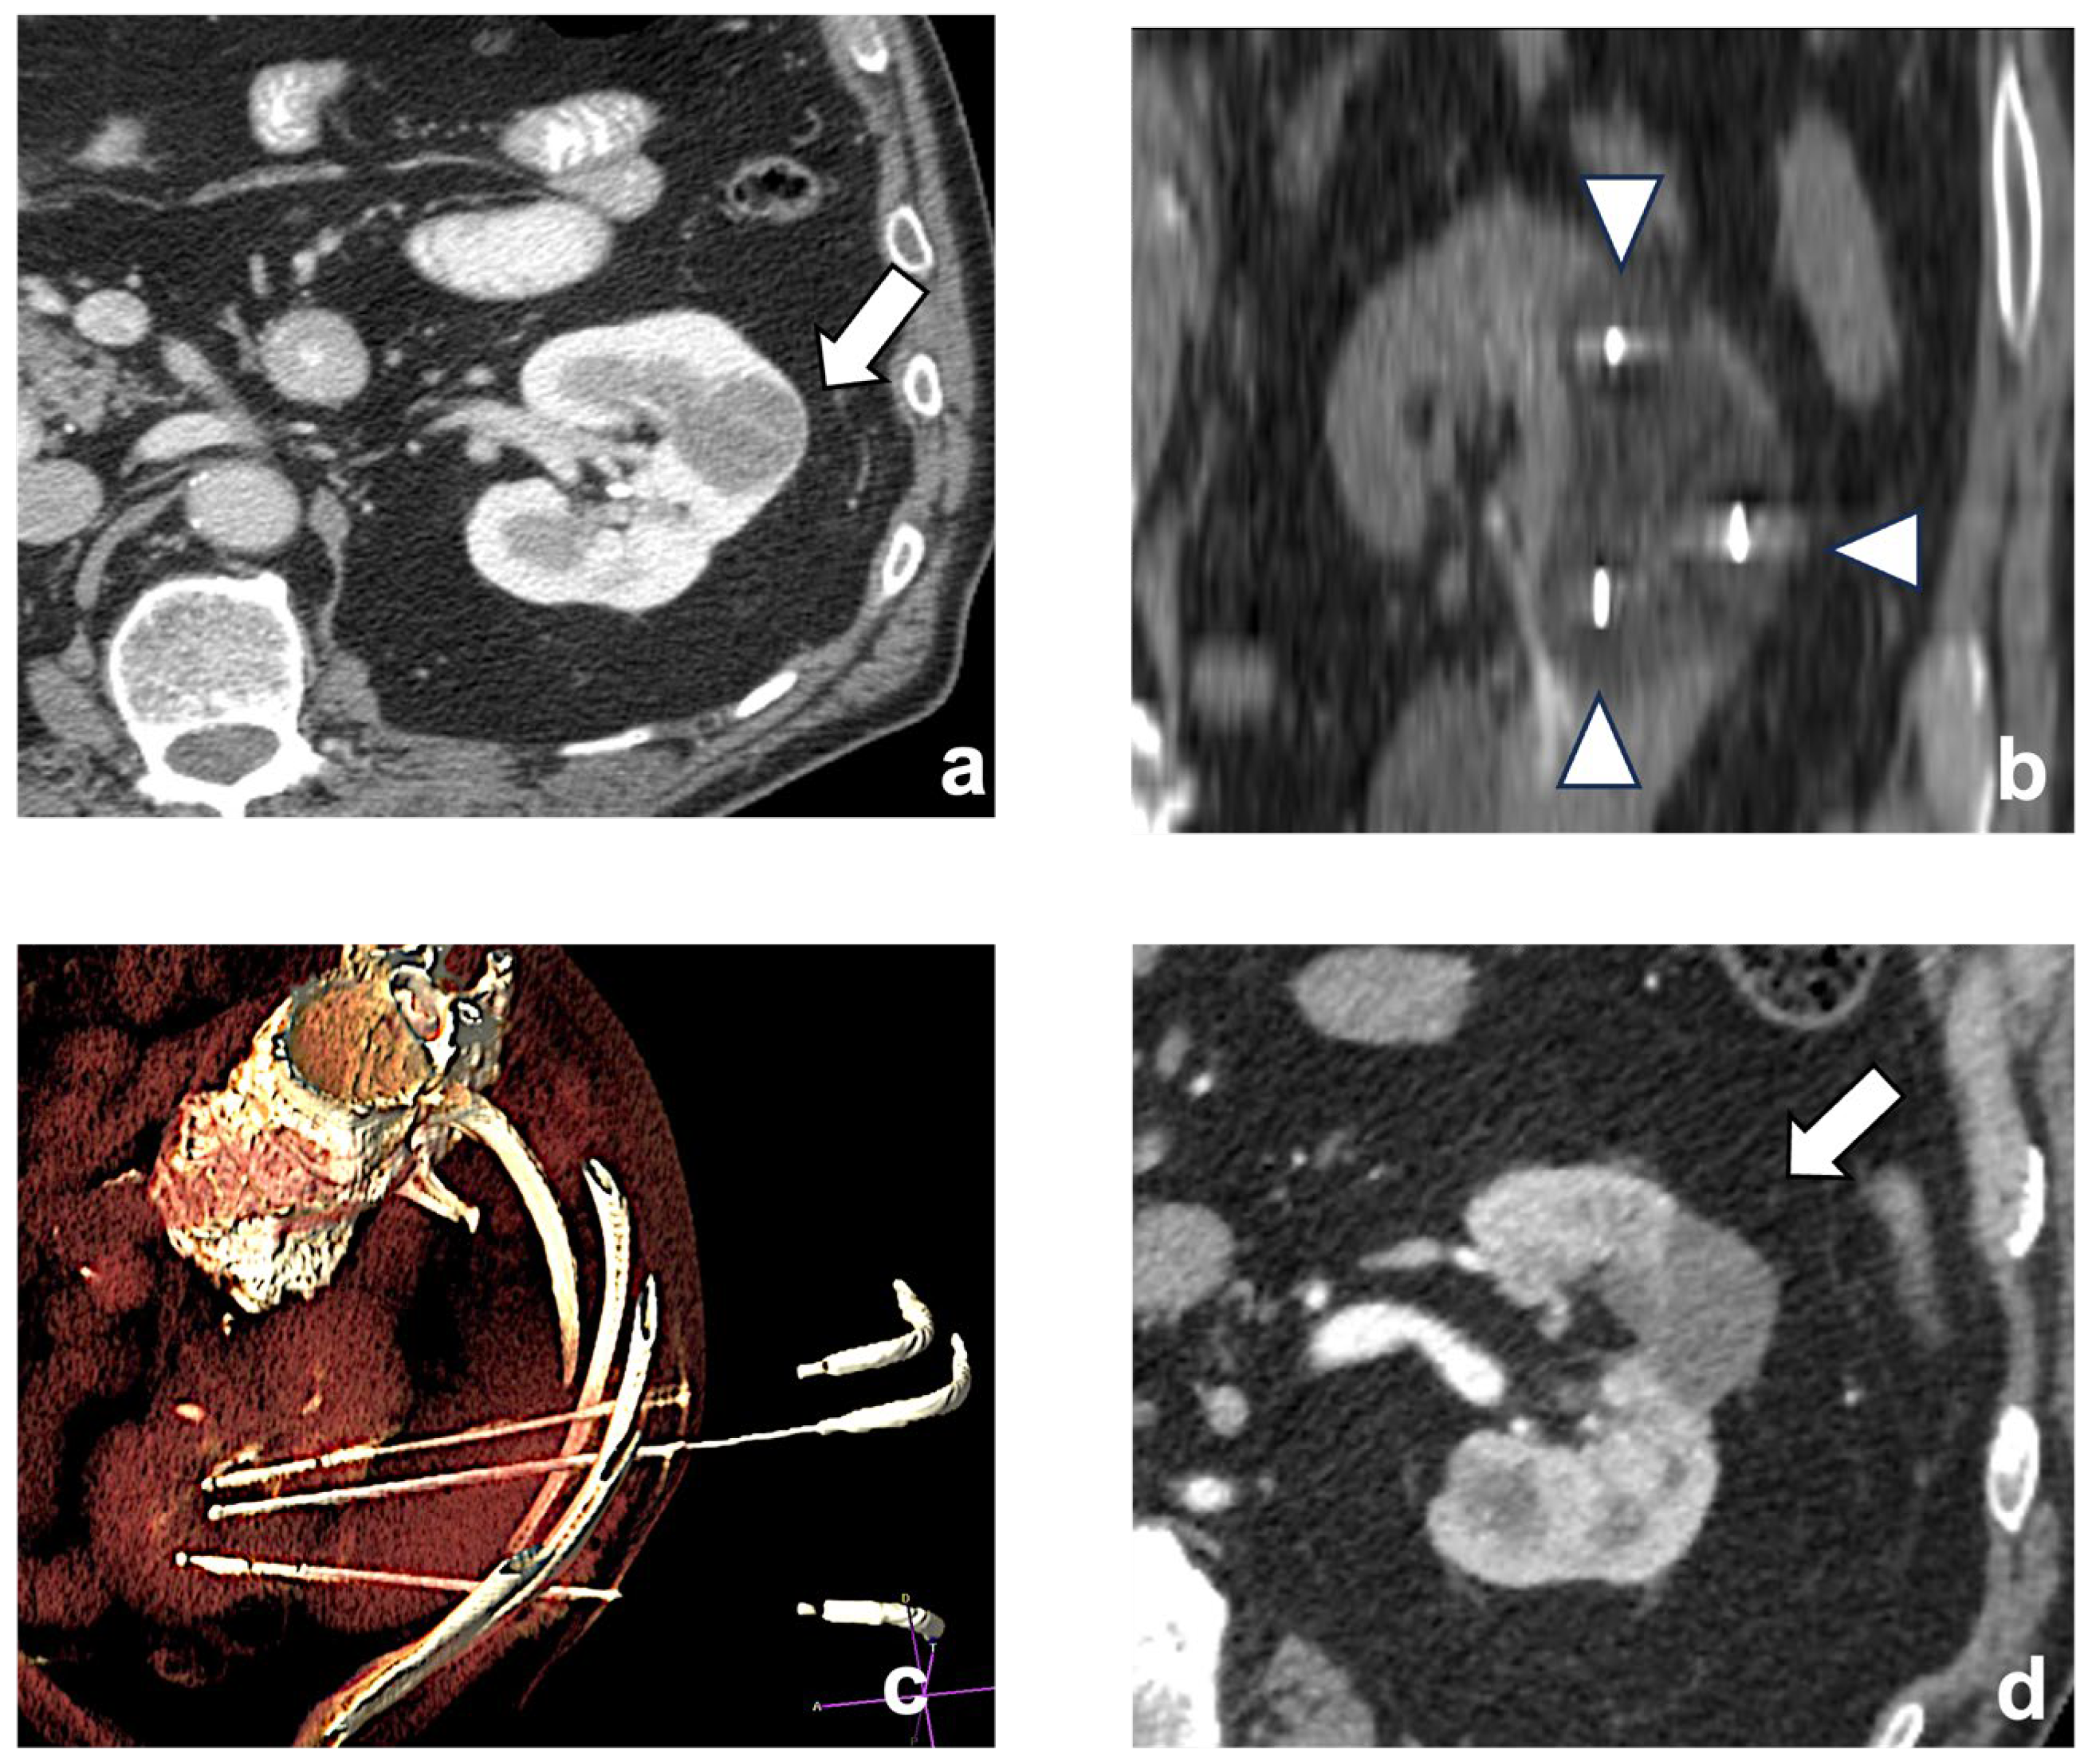

Historically, size is a well-known factor of technical unsuccess and tumor recurrence. This is particularly true when the ablative treatment is performed with RF. On the other hand, CA allows for the extension of the ablation area using multiple cryoprobes, generating ice balls that are large enough to treat tumors as large as 8 cm in size [31] (Figure 2).

Figure 2.

A left chromophobe RCC (arrow), hypovascular compared to normal renal cortex (a). Three cryoablation probes (arrowheads) are placed in the tumor, creating an ice-ball ((b) coronal plane). A volume-rendering reconstruction represents the probes’ access and positioning in the renal mass (c). Post-contrast CT shows the positive outcome of the ablation (arrow (d)).